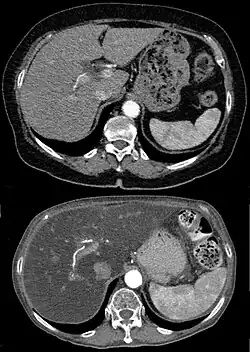

Ausgeprägte Fettleber in der Computertomographie (unten) im Vergleich zu einer normalen Leber (oben).

Eine Leberverfettung fällt meistens in einer Sonographie durch Vergrößerung und erhöhte Echogenität im Vergleich mit der Niere[12] sowie durch eine plumpe Form oder in einer Computertomographie oder Magnetresonanztomographie auf. Wenn aus anderen Gründen eine Biopsie der Leber durchgeführt wird, lässt sich die Fettleber auch histologisch sichern. Laborchemisch lässt sich kein sicherer Nachweis führen, allerdings fallen oft leicht erhöhte Transaminasen und eine erhöhte γ-GT auf.[13] Es gibt auch die Möglichkeit, mit Hilfe von Körpergröße, Körpergewicht, γ-GT, Triglyceriden und Bauchumfang den Fettleber-Index zu berechnen, der die Wahrscheinlichkeit für das Vorliegen einer Fettleber vorhersagen kann.[14] Der Schweregrad kann mittels spezieller Kernspintomographie- oder Elastographie-Methoden bestimmt werden.[15]